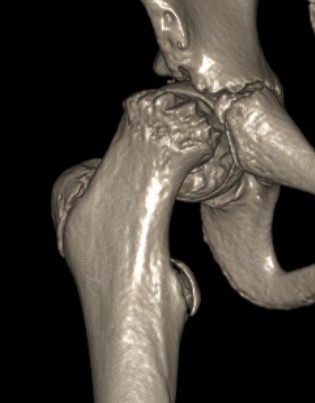

Deformity

Varus / extension / external rotation

Osteotomy

Valgus / flexion / internal rotation

Intertrochanteric / Southwick

Base of neck / Kramer

Intra-capsular / Subcapital